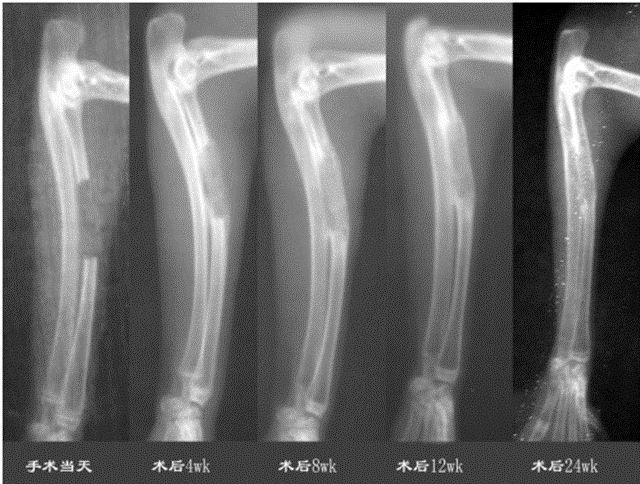

清華大學(xué)熊卓和第四軍醫(yī)大學(xué)利用PLLA/TCP復(fù)合材料,PLLATCP的質(zhì)量比為7:3,制造支架的開放孔隙的孔隙率為80%,大孔孔徑約為500 μm,微孔孔徑約為5 μm。支架的外形為直徑5mm、長15mm的圓柱形;生長因子為rhBMP-2。結(jié)果顯示術(shù)后4周,骨缺損區(qū)有不均勻的低密度骨痂顯影;術(shù)后8周,骨痂顯影密度增高,骨痂外層形成皮質(zhì)骨輪廓,與缺損斷端連接;術(shù)后12周,骨痂密度進(jìn)一步增高,中心區(qū)出現(xiàn)與植入支架輪廓一致的高密度區(qū),周圍皮質(zhì)骨輪廓清晰,與斷端連接良好;術(shù)后24周,骨痂塑型完好,骨痂皮質(zhì)骨與缺損兩斷端的皮質(zhì)骨完全融合成一體,骨痂中心區(qū)密度降低。